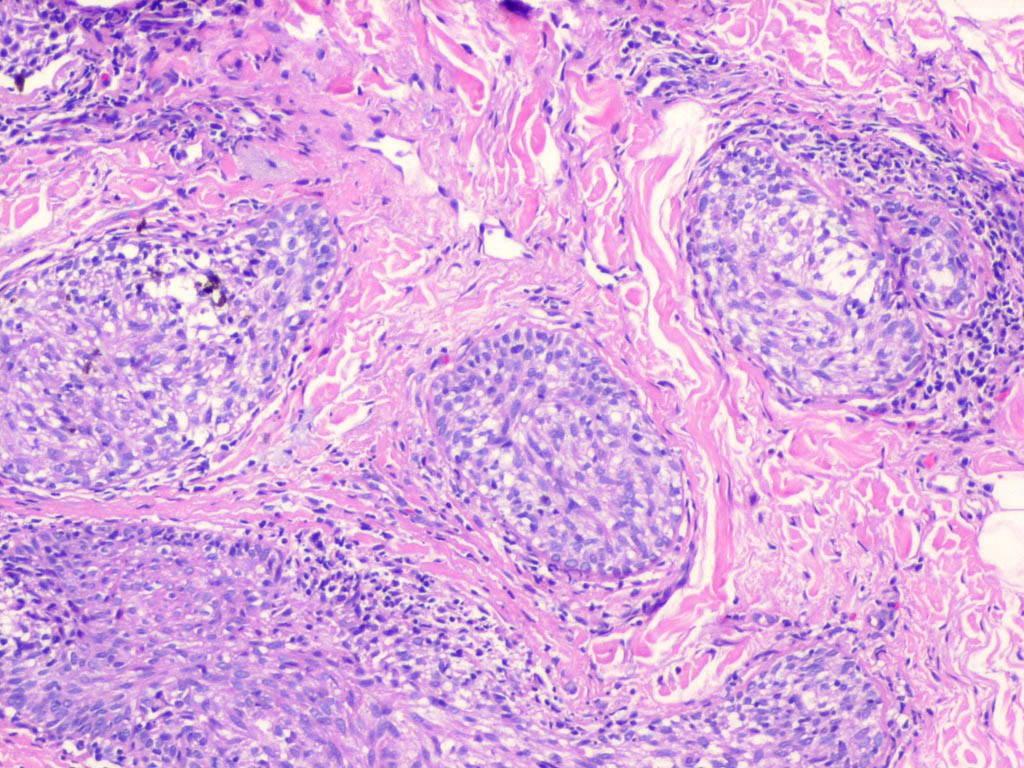

Cutaneous lymphadenoma =الغدوم اللمفاوي الجلدي